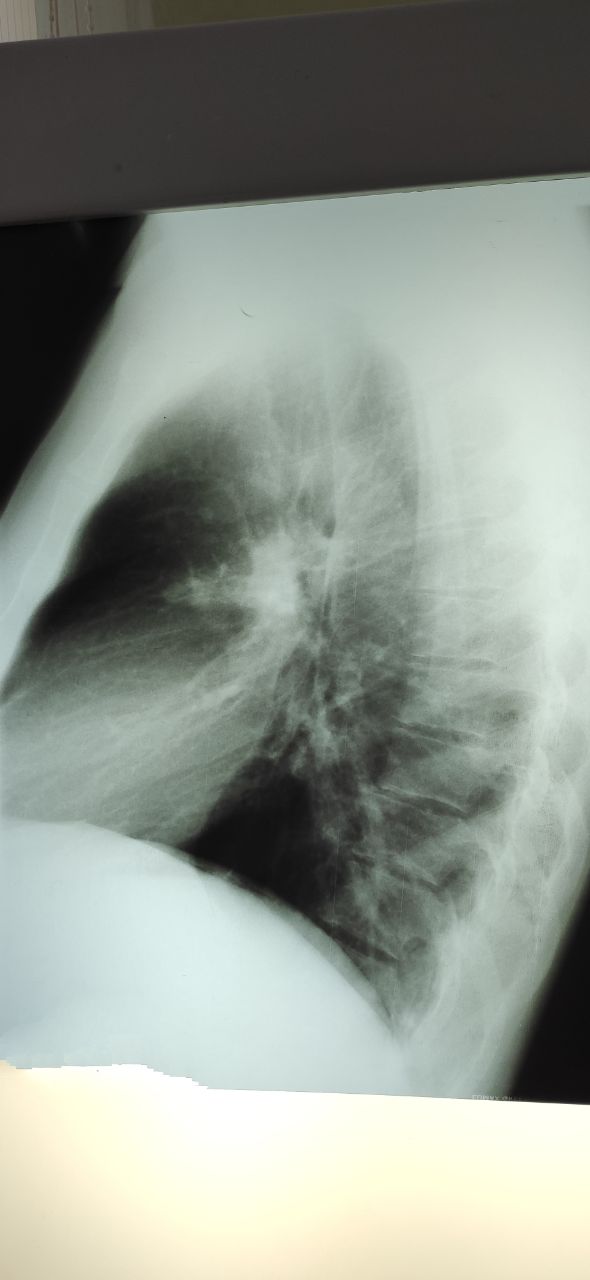

Пациент, 37 лет, жалоб не предъявляет, отправили на контроль. Злоупотребляет алкоголем. Это снимки сегодня

Маруська in Radiology/Рентгенология Чат

Это снимки в ноябре, лечили пневмонию

Нужна консультация фтизиатра? Или думать в другом направлении?

Вообще без динамики. А ранее любые есть снимки?

Снимки есть, но я не сфоткала. Там этих теней не было

Процесс активный значит

Можно предположить что мои или бои, но не характерное расположение

Диаскин, пцр, кт и мокроту

Значит фтизиатр однозначно и кровь на вич

То что алкоголь в анамнезе уже звоночек